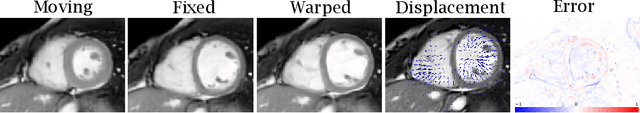

Abstract:Quantification of cardiac motion with cine Cardiac Magnetic Resonance Imaging (CMRI) is an integral part of arrhythmogenic right ventricular cardiomyopathy (ARVC) diagnosis. Yet, the expert evaluation of motion abnormalities with CMRI is a challenging task. To automatically assess cardiac motion, we register CMRIs from different time points of the cardiac cycle using Implicit Neural Representations (INRs) and perform a biomechanically informed regularization inspired by the myocardial incompressibility assumption. To enhance the registration performance, our method first rectifies the inter-slice misalignment inherent to CMRI by performing a rigid registration guided by the long-axis views, and then increases the through-plane resolution using an unsupervised deep learning super-resolution approach. Finally, we propose to synergically combine information from short-axis and 4-chamber long-axis views, along with an initialization to incorporate information from multiple cardiac time points. Thereafter, to quantify cardiac motion, we calculate global and segmental strain over a cardiac cycle and compute the peak strain. The evaluation of the method is performed on a dataset of cine CMRI scans from 47 ARVC patients and 67 controls. Our results show that inter-slice alignment and generation of super-resolved volumes combined with joint analysis of the two cardiac views, notably improves registration performance. Furthermore, the proposed initialization yields more physiologically plausible registrations. The significant differences in the peak strain, discerned between the ARVC patients and healthy controls suggest that automated motion quantification methods may assist in diagnosis and provide further understanding of disease-specific alterations of cardiac motion.